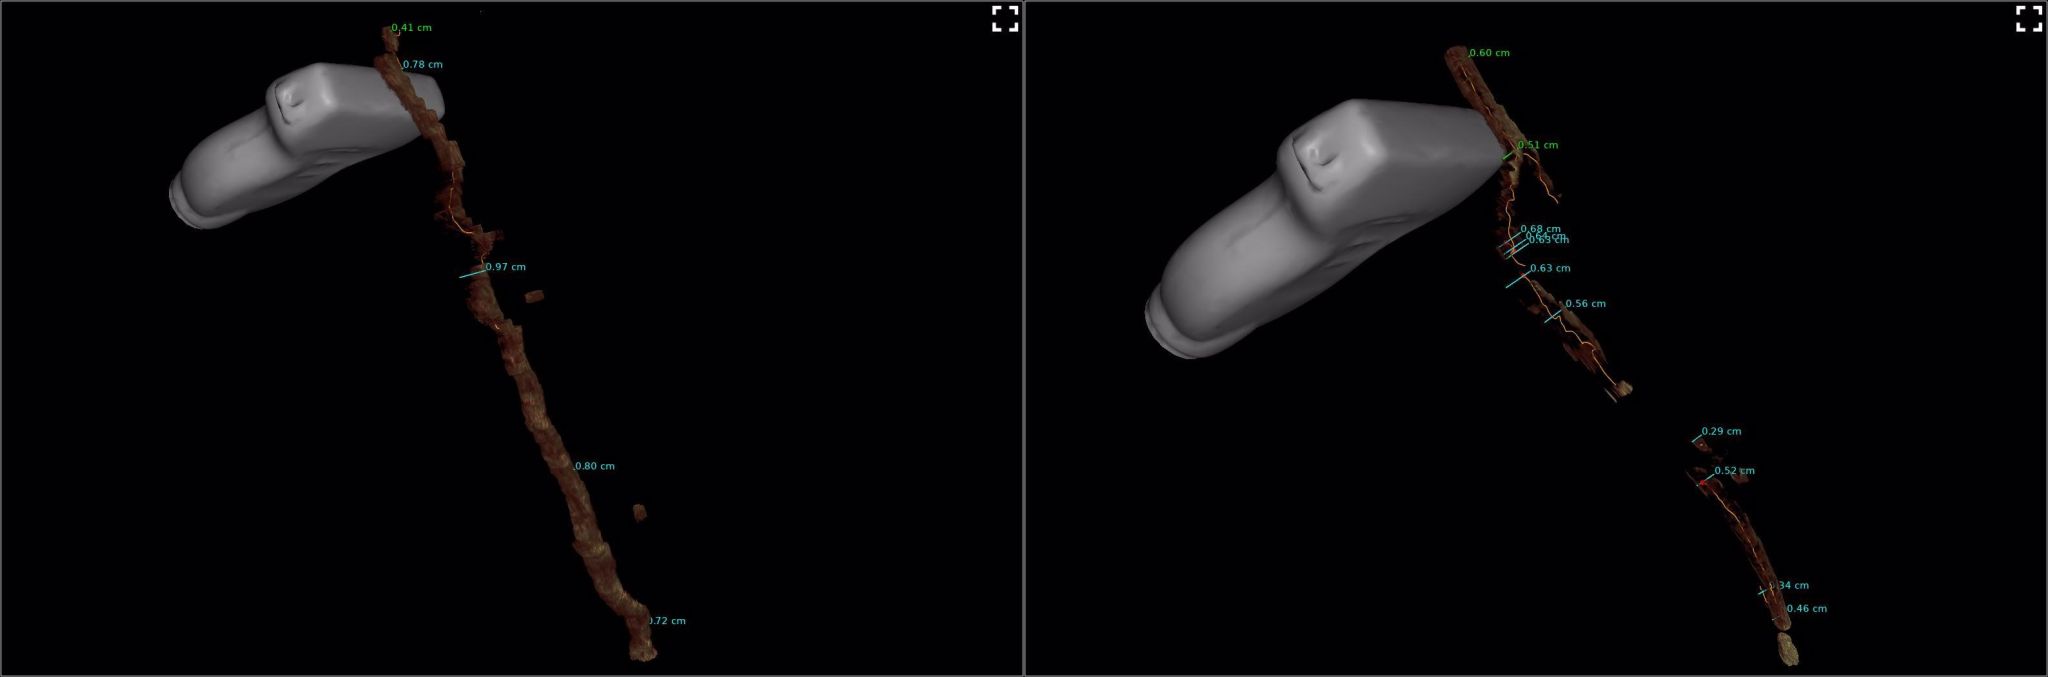

Traitement en direct d’une grande veine saphène (GVS) avec analyse 3D avant et après injection, permettant de mettre en évidence :

Avant l'injection

Le trajet en volume de la GVS sur les trois plans de l’espace, ses diamètres précis, mesurés grâce à l'IA de manière digitale, sur plusieurs points

La réduction du calibre de manière objective grâce aux calculs numériques de l’IA.